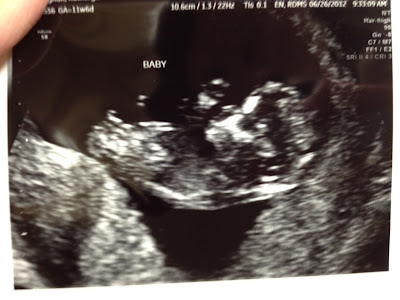

Had our NT scan today, and baby is measuring right on track! HB was 171- nice and strong. It feels so good to know all is well in there!